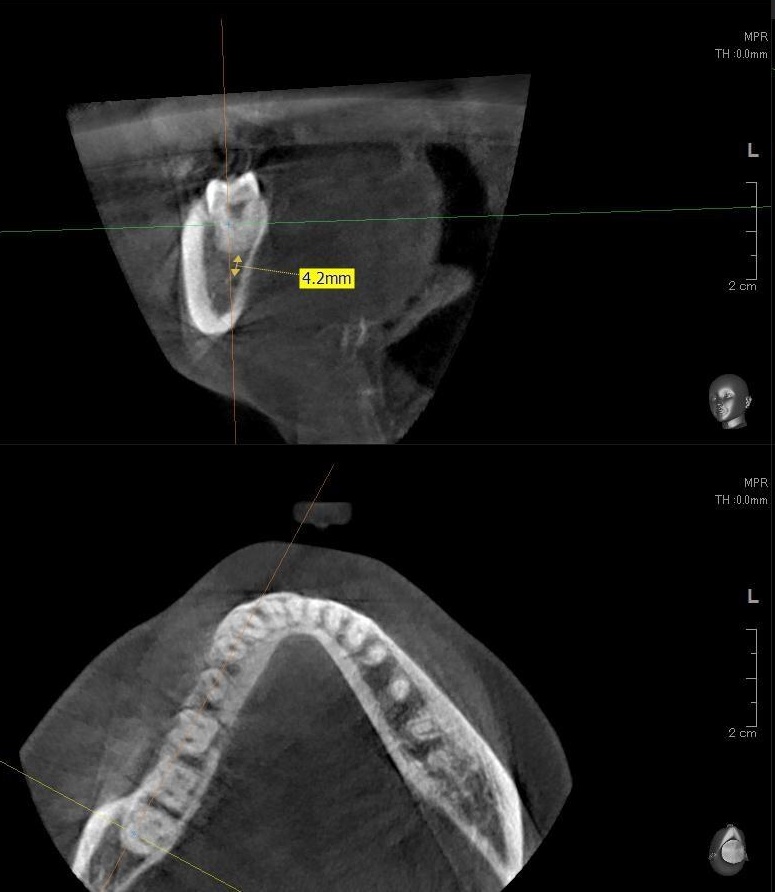

さらに、下顎の親知らずは下歯槽神経に非常に近いところに生えている場合もあるため、CTも撮影し詳しい解析を行います。

親知らずが生えている位置が、神経に近い、あるいは神経に当たっている場合は、大きな病院に紹介する場合もあります。

親知らずの根っこは下歯槽神経から近い距離にありますが、抜歯は可能との診断でした。